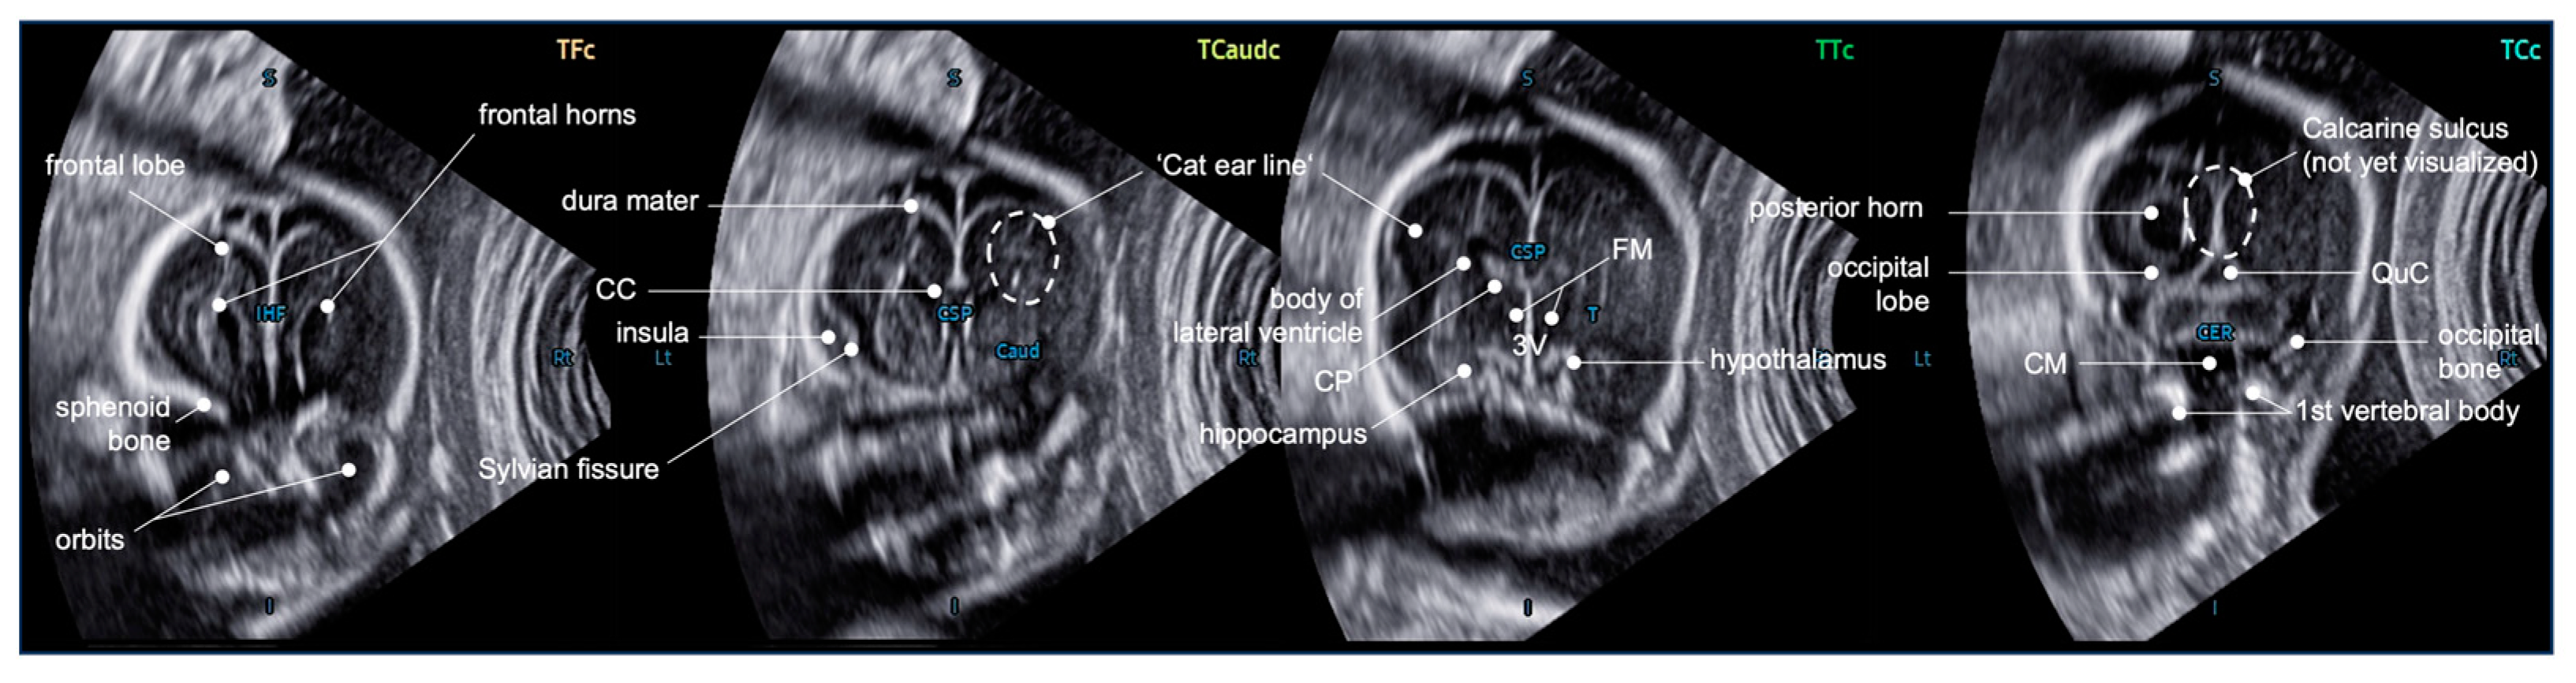

4.3. Additional Value of the Coronal Planes